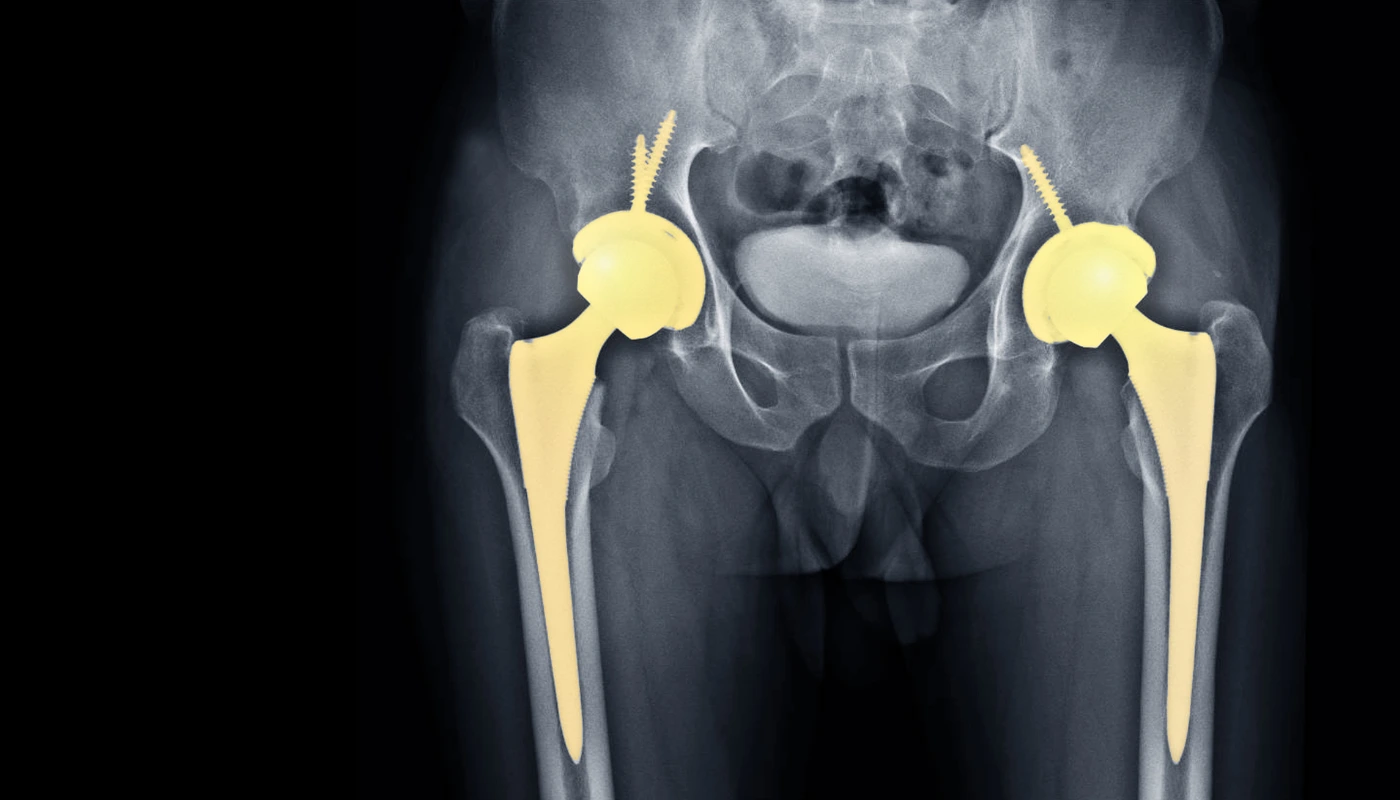

A Total Hip Replacement is a major reconstructive surgery where the damaged bone and cartilage of the hip joint are removed and replaced with prosthetic components. The hip is a “ball-and-socket” joint; in a healthy hip, the femoral head (the ball) rotates smoothly within the acetabulum (the socket) of the pelvis. When this joint becomes diseased or injured, the smooth cartilage that cushions the bones wears away, leading to a “bone-on-bone” environment.

During the THR procedure, the surgeon removes the arthritic femoral head and replaces it with a metal or ceramic ball attached to a stem that fits into the femur. The damaged socket is hollowed out and replaced with a metal shell, into which a durable plastic, ceramic, or metal liner is inserted. These new bearing surfaces allow for friction-free movement, mimicking the natural mechanics of a healthy human hip. At Physio Expert, we view the new joint as a high-performance tool that requires specific “tuning” through physiotherapy to reach its full potential.